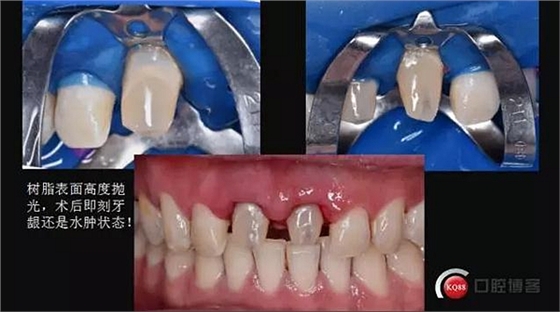

粘結(jié)前的準(zhǔn)備

酸蝕時(shí)間死髓牙60秒,活髓牙五到十秒,上障比較困難全程在強(qiáng)吸下操作,確保粘結(jié)強(qiáng)度

本次使用的是bisco雙固化樹脂,60秒后初步固化,12號(hào)刀片和牙線去除多余粘結(jié)劑

去除隔離膜,涂布阻氧劑后各個(gè)方向固化,每個(gè)方向60-90秒

術(shù)后即刻照,口腔衛(wèi)生宣教!